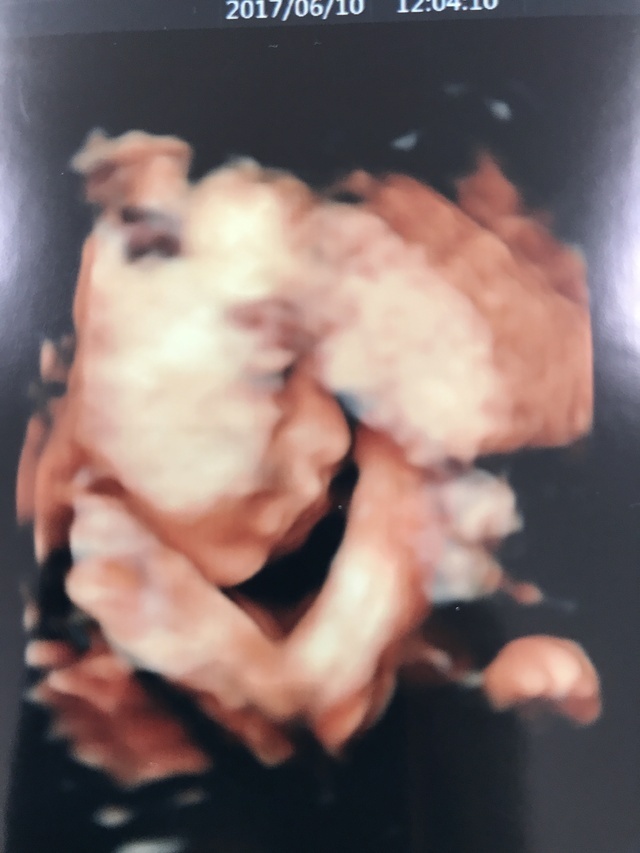

26週2日(26w2d・女の子)|ゆゆあ さん(26歳)

エコー写真撮影時のエピソード:

里帰りして病院がかわりドキドキの中、前の病院ではなかった4Dエコー。お顔は見せてくれなかったけれど、立体的な我が子に感動しとてもうれしかったのを覚えています。

生まれてきて会えるのがさらに楽しみになりました。